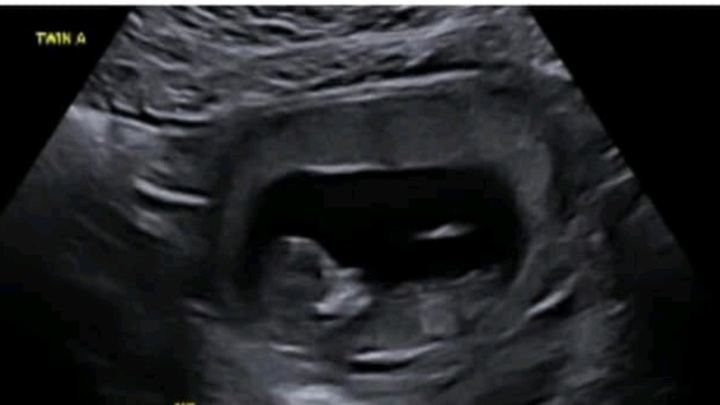

On the 9/02/2025 our twin pregnancy (18 weeks +6 days) Clare’s waters broke suddenly. We have been admitted to Taree hospital via arrival by ambulance and the result was confirmed and 1cm dilated.

Since then we have experienced the natural result of a bleed and fluid loss for our beautiful little twin A, however at this stage both twins still have heartbeats and have managed to not arrive earth side yet. Clare is on antibiotics to prevent any infections with waters breaking and our babies becoming partly exposed to the world, and just taking everything hour by hour.